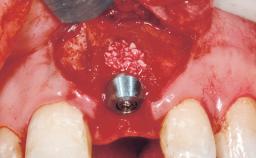

A 30-year-old female patient had lost tooth 21 and was referred to our clinic for consultation and treatment. Due to advanced apical infection, tooth 21 had been extracted two months earlier at another clinic and an acrylic-resin tooth had been bonded to the adjacent teeth. The patient desired implant treatment to avoid any damage to the adjacent natural teeth. While the patient had no history of any systemic disorder, she was a heavy smoker and exhibited medium to advanced periodontitis in the entire jaw. After the initial treatment to achieve a pocket probing depth of less than 4 mm and no bleeding on probing, a decrease in the height of the papillae mesial and distal to the extraction site and overall gingival recession were observed.